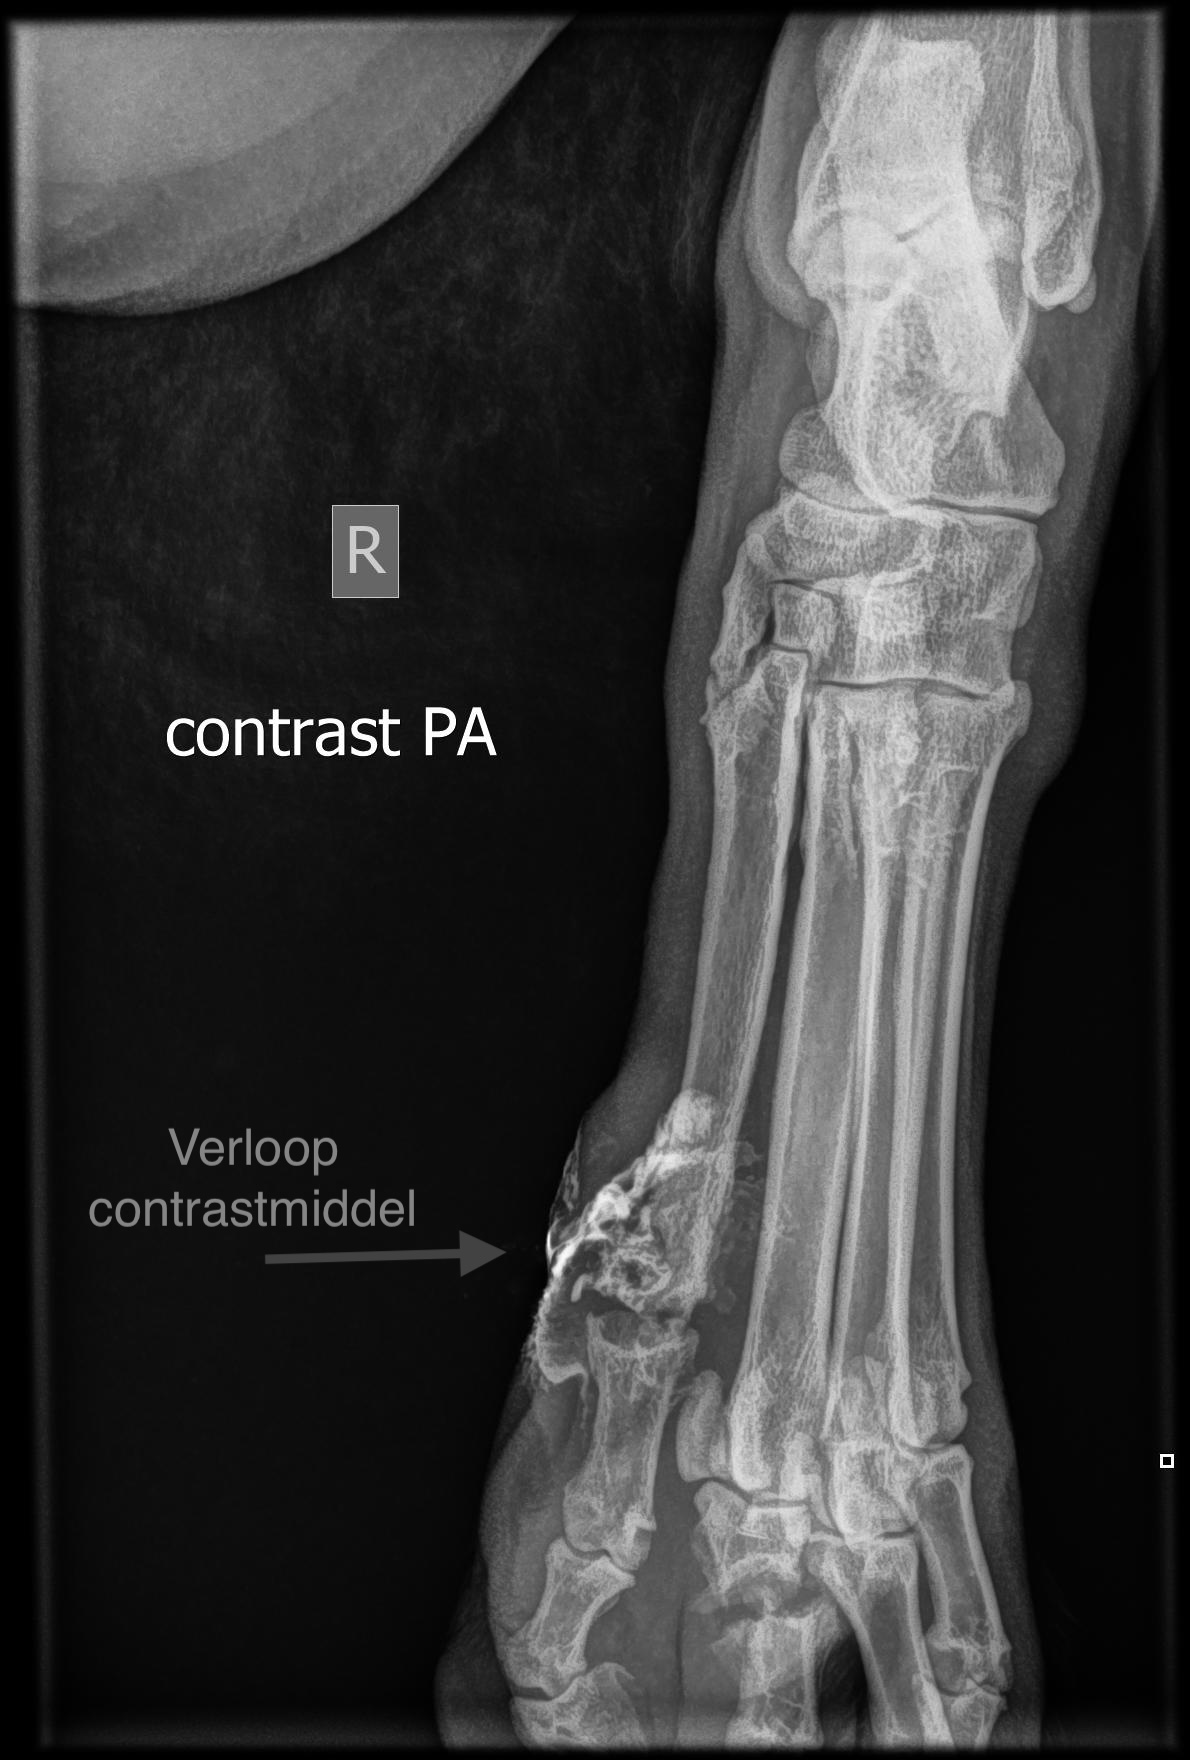

In juli 2025 zagen we Muk en zijn teen voor het eerst. We waren wel onder de indruk van Muk: een grote Leonberger, die je met zachte ogen aankeek. Krijg dat maar eens in beweging, als je hart al niet wegsmelt. Maar 85 kg kan ook heel meewerkend zijn, dat bewees onze Muk. We hebben eerst een kweek afgenomen om te zien met welke bacterie we een wedstrijd aan moesten gaan. En daarna gestart met het zoeken naar de oorzaak van een infectie onder de huid. Vaak is dit bij honden een vreemd voorwerp dat onder de huid is gekropen, waarbij grasaren 🌾 daar berucht om zijn. Maar als snel bleek dat de bacterie rondom de hele teen fistelgangetjes had gemaakt met zelfs botoplossing van een teenkootje. Dit komt zelden voor bij dieren, maar als het optreedt is het moeilijk om daarvanaf te komen. Omdat met locale behandeling niet tot een goed resultaat leidt en de binnenste teen geen dragende teen is, is besloten om de teen met alle fistelgangetjes te verwijderen.

Maar tot onze schrik zagen we op de röntgenfoto ook dat een teenkootje van de andere teen gebroken was. Als hij een teen mist, zal deze gebroken teen harder moeten werken. We hadden nu twee problemen: een fistelende teen met bacteriën (te zien aan het contrastmiddelverloop) en een gebroken teenkootje. We gingen aan de slag: de teen werd verwijderd en een spalk voor de ondervoet werd aangemeten. Het gebroken kootje kon daardoor rust krijgen en gaan helen, terwijl we de operatiewond konden verbinden.